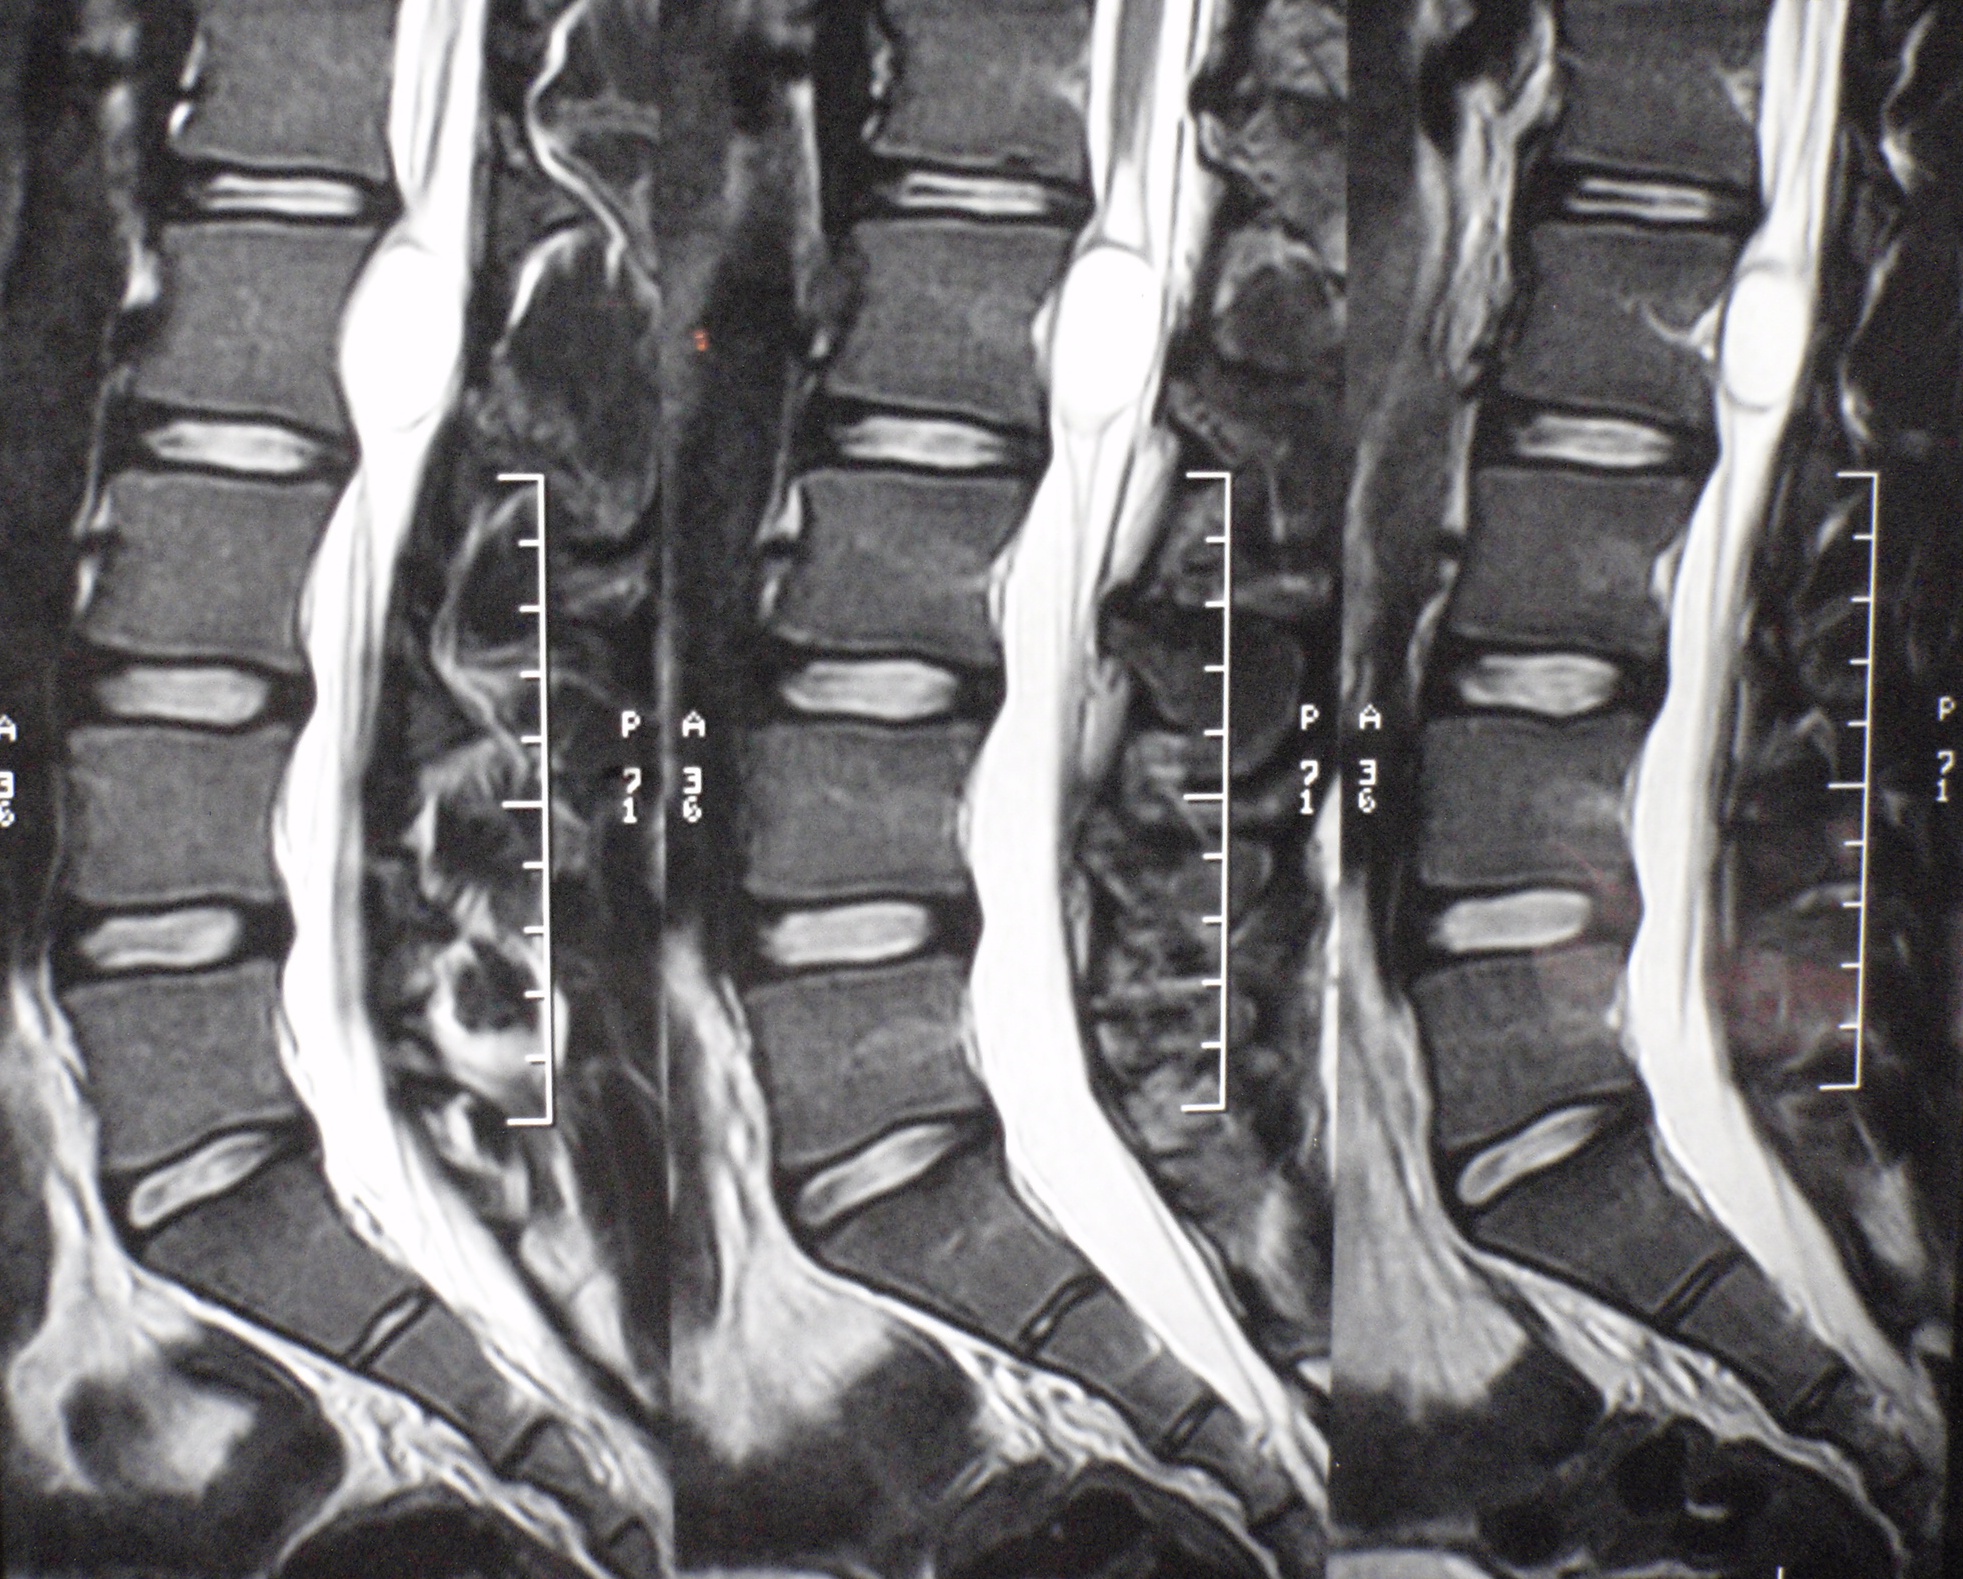

El quiste neuroentérico espinal es una lesión de rara presentación, existiendo sólo reportes de casos aislados. Estos representan del 0,3 al 1,3% de los tumores espinales según las distintas citas bibliográficas.Suelen afectar el canal espinal, especialmente a nivel cervical bajo y torácico superior.El 90% aproximadamente de estos quistes se localizan en el espacio intradural-extramedular, mientras que el 10% restante se divide entre la localización intradural-intramedular o extradural.El tratamiento de los quistes neuroentéricos intraespinales es quirúrgico, mediante la resección lo mas radical posible. Los resultados son favorables y la recurrencia después de la resección parcial puede tardar años en hacerse sintomática.Descargas